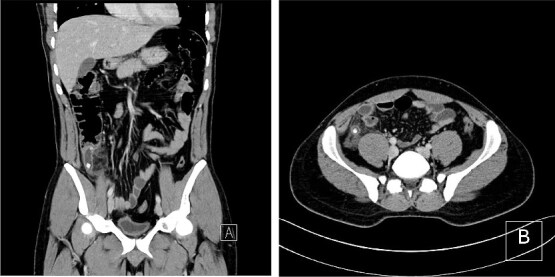

Comamonas testosteroni is an uncommon environmental Gram-negative bacillus rarely implicated in human infections. We report a case of a 34-year-old male who presented with acute appendicitis complicated by a sealed perforation. Laparoscopic appendectomy was performed, and postoperative cultures identified C. testosteroni in the appendiceal tissue, alongside Pseudomonas aeruginosa and Streptococcus anginosus in the peritoneal fluid. Initial empirical antibiotics were escalated to piperacillin-tazobactam based on culture results. The patient recovered uneventfully and was discharged on postoperative day nine. This case highlights the emerging clinical relevance of C. testosteroni and the importance of microbiological evaluation in guiding management of perforated appendicitis.